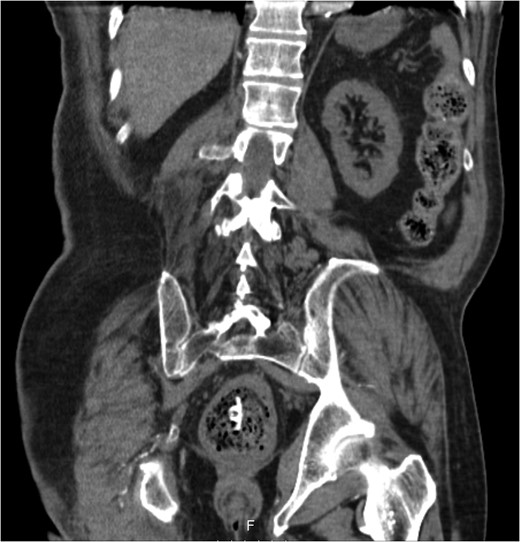

A 68-year-old male nursing home resident presented following dislodgement of a percutaneous endoscopic colostomy (PEC) tube originally sited to prevent recurrent sigmoid volvulus. Computed tomography demonstrated tube migration into the lumen of the recto-sigmoid junction, where it remained for 12 days before passing spontaneously. During this period, the patient remained asymptomatic; the residual colocutaneous fistula functioned as a decompressive valve. Originally, the patient was due to be discharged with early flexible sigmoidoscopy follow-up. However, complex social issues delayed discharge. During his admission, a second PEC tube was successfully inserted next to the previous colostomy site without complication. This is an unusual case and no similar episodes of asymptomatic PEC migration have been reported. We demonstrate that such cases may be offered an appropriate trial of conservative management. Here, we describe our experience and critically appraise the literature.

The patient remained asymptomatic with a soft, non-tender abdomen. The only abnormal clinical finding was the absence of a PEC tube from a patent periumbilical colostomy site.

The patient remained well and the PEC tube passed spontaneously on Day 12, during a bowel motion.

Tube migration leading to perforation and frank peritonitis has been described elsewhere [10]. However, there are no cases of asymptomatic dislodged PEC tubes. Following discussion with gastroenterology and colorectal surgery, the decision was made to let the PEC pass spontaneously or remove it during early follow-up flexible sigmoidoscopy. The PEC tube was naturally expelled on Day 12 without complication.